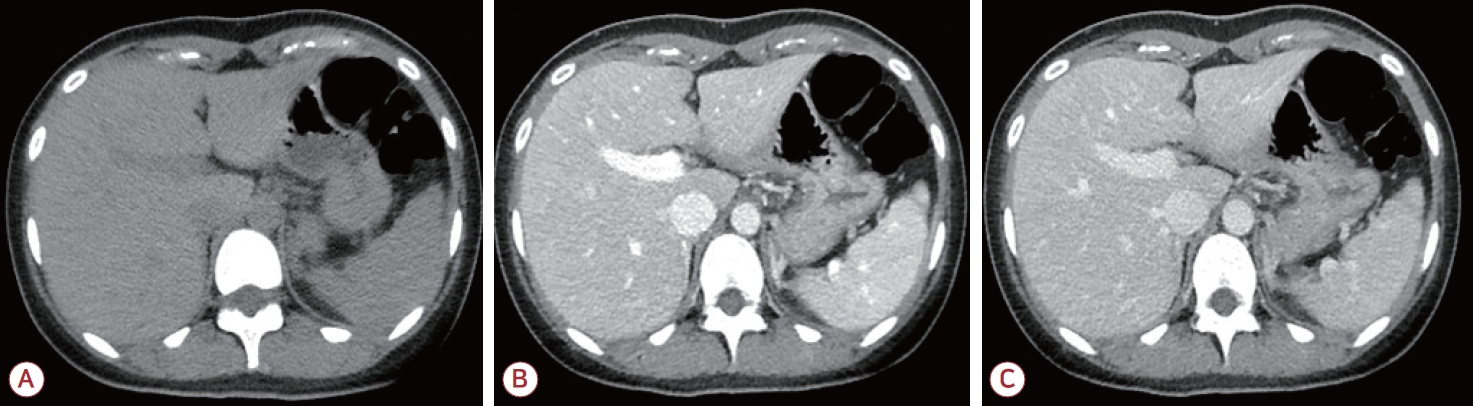

19세 여자가 갑자기 발생한 의식 변화를 주소로 응급실에 왔다. 의식은 멍하고 정신기능의 속도가 저하되어 반응이 느렸으며 상황에 적절한 대답을 하지 못하는 혼돈 상태를 보였다. 신경계진찰에서 퍼덕떨림(flapping tremor)을 보였고 다른 이상 소견은 없었다. 가족력에서 의식 변화를 유발할 만한 특이 병력은 확인되지 않았다. 과거력상 4-5세경 수일 동안 멍하고 반응이 떨어지는 증상을 보였으나 특별한 조치 없이 회복된 적 있었고, 당시 특별한 진단은 받지 못하였다고 하였다. 이후 현재까지 정상적인 발달 과정을 거쳤으며, 특이 병력이나 현재 복용 중인 약물은 없는 상태이다. 뇌 조영증강 전산화단층촬영 및 뇌 조영증강 자기공명영상에서 구조적 이상 소견은 없었으며(Fig. 1), 뇌척수액 검사에서 뇌압은 150 mmH2O, 백혈구 1/mm3, 총 단백질 28.3 mg/dL, 포도당 71 mg/dL, 혈청포도당 118 mg/dL로 중추신경계 감염 및 염증의 증거는 없었다. 혈액 검사에서는 간기능은 정상이나 혈중 암모니아 농도가 290 μg/dL로 정상 수치의 4-5배가량 상승하여 있었다. 이에 대해 복부 조영증강 전산화단층촬영을 시행하였으나 간 및 간문맥 등의 구조적 이상은 보이지 않았다(Fig. 2). 뇌파 검사에서는 전반적인 세타파(theta slowing, 4-7 Hz) (Fig. 3-A)를 보여 고암모니아혈증으로 인한 대사 뇌병증(metabolic encephalopathy) 진단하에 경구 락툴로스(lactulose) 투약을 시작하였다. 그 외 국소 시작발작이 발생하였을 가능성을 배제할 수 없어 레비티라세참(levetiracetam) 투약도 같이 시작하였다. 입원 2일째 추적 혈액 검사에서 혈중 암모니아 수치는 174 μg/dL로 감소하였으며, 의식 수준도 명료하게 평소와 같은 수준으로 회복되었다. 추적 뇌파 검사도 정상이었다(Fig. 3-B).

Figure 1.

Brain magnetic resonance imaging of the patients. (A) T1-weighted axial image, (B) T2-weighted axial image, (C) T2-weighted fluid attenuated inversion recovery image, (D) T1 gadolinium-enhanced axial image. There is no demonstrable lesion causing neurologic deficit such as confusion.